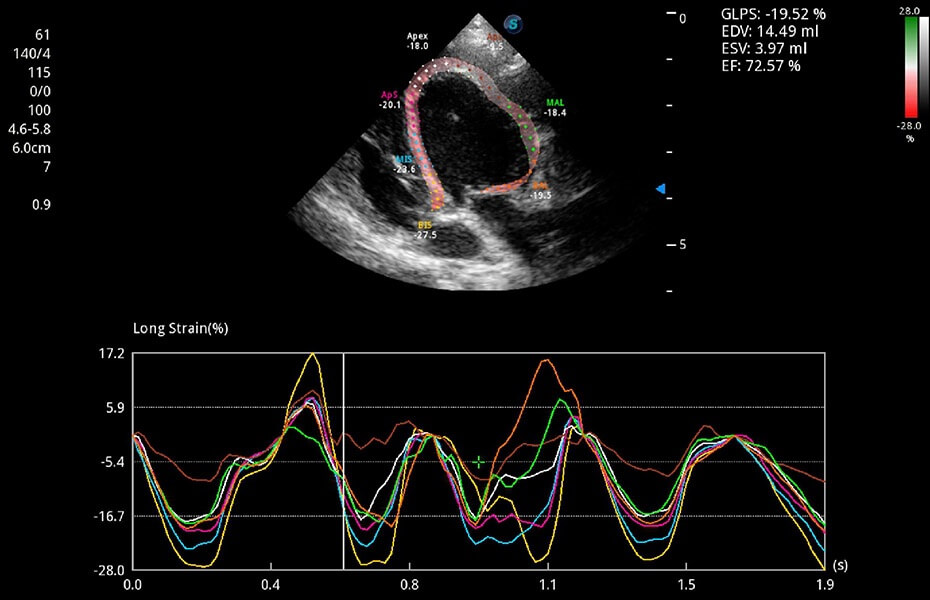

ProPet 60 作为一款高端台式动物超声设备,为动物医生的日常诊断提供了一系列贴合动物临床需求、解决临床实际问题的高级成像功能。凭借全系列高清探头,满足医生对腹部、心脏、生殖、浅表、肌骨等成像的所有需求,切实帮助您提升检查效率,提高诊断信心。